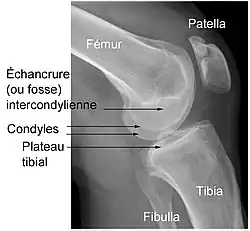

Éléments d'anatomie du genou

(vue inférieure fémur droit)

Le genou naturel est composé de trois parties osseuses :

- l’extrémité inférieure du fémur qui a la forme de deux roues accolées : les condyles ;

- l’extrémité supérieure du tibia, encore appelé plateau tibial ;

- la patella (ou rotule) : petit bouclier situé sur l’avant du fémur.

Vue supérieure du plateau tibial (membre inférieur droit)

À ceci s'ajoutent d'autres éléments, favorisant le fonctionnement parfois très contraignant de l'articulation (voir schéma) :

- Une couche de cartilage recouvrant chaque partie osseuse en regard d'une autre : condyles fémoraux, partie antérieure du fémur, face postérieure de la patella et plateau tibial.

- Deux petits coussins de cartilage fibreux, les ménisques, disposés entre le fémur et le tibia. En forme de croissant mobile — seules les cornes s'insèrent sur le plateau tibial —, ils augmentent la congruence articulaire et amortissent le contact entre le cartilage du fémur et celui du tibia. Ils sont situés l'un vers l’intérieur (ménisque médial ou interne, qui répond au condyle médial du fémur) et l'autre vers l’extérieur du genou (ménisque latéral ou externe, en regard du condyle latéral).

- Des ligaments assurant la stabilité de l’articulation, et dont les principaux sont :

- deux ligaments croisés :

- le ligament croisé antérieur (LCA) — ligament croisé antéro-externe (LCAE), dans l'ancienne nomenclature —, son origine se trouve sur la surface pré-spinale de l'espace intercondylaire du plateau tibial, entre les cornes méniscales. Il se dirige en haut, en arrière et en dehors pour venir s'insérer sur la surface intercondylienne du condyle fémoral latéral. Le LCA croise en dehors le :

- ligament croisé postérieur (LCP) — ou ligament croisé postéro-interne (LCPI) de l'ancienne nomenclature —, de son origine, sur la surface rétrospinale de l'aire intercondylaire, il se dirige en haut, un peu en avant et en dedans, pour s'insérer sur la surface intercondylienne du condyle fémoral médial.

- Deux ligaments collatéraux : ligament collatéral tibial (ou interne) et ligament collatéral fibulaire (ou externe) maintenant le genou en dedans et en dehors. Les ligaments collatéraux sont également croisés, permettant une bonne stabilité du genou.

- Les ligaments maintenant la patella : le tendon patellaire (rotulien), reliant la patella au tibia et les tendons du muscle quadriceps reliant la patella à la cuisse. Ils assurent la transmission de la traction du quadriceps sur le tibia même en position de forte flexion du genou, la patella agissant comme poulie.

- Une capsule articulaire contenant le liquide synovial qui baigne l'intérieur de l’articulation et y favorise les glissements.

Les facteurs anatomiques sont soupçonnés déjà depuis longtemps. La résistance à la rupture d'un LC dépend directement de sa largeur, qui varie d'un individu à l'autre. Dans une étude anthropométrique, les LCA du genou controlatéral intact de patients victimes d'une rupture de LCA ont été comparés avec ceux d'individus de même poids corporel. Les volumes des LC ont été déterminés par IRM. Dans le groupe des blessés, le volume des LCA contralatéraux était en moyenne 1 921 mm3, tandis que dans le groupe de contrôle, il était de 2 151 mm3. Les auteurs de l'étude en concluent que les différences anthropométriques des volumes – et de la largeur qu'on en déduit – des LC ont une influence directe sur la probabilité d'une rupture de LC sans agression externe[49]. Déjà dans des études précédentes, on a établi une corrélation entre cavité ligamentaire du fémur (notch intercondylaire : voir figure) étroite, liée à des ligaments plus étroits, et un risque plus élevé de rupture de LC[50],[51],[52],[53],[54],[55]. Cependant on n'est pas arrivé à un consensus scientifique, parce que d'autres études aboutissent à des résultats opposés[43],[56],[57]. Par rapport aux hommes, les femmes ont une cavité ligamentaire plus étroite, ce qui pourrait expliquer une incidence plus élevée des ruptures de LC chez les femmes[58],[59].